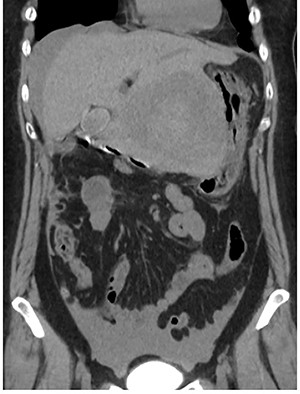

A 56-year-old woman presented to another hospital with acute abdomen. Computed tomography (CT) examination demonstrated a tumor 10 cm in diameter that protruded from the left lateral segment of the liver, with evidence suggestive of rupture of the liver tumor (Fig. 1). Since the patient was in good general condition, she was referred to our hospital for further evaluation. Her blood biochemical parameters when she was referred to our hospital were hemoglobin: 11.6 g/dl, albumin: 3.4 g/dl, γ-globulin: 18.5% and anti-acetylcholine receptor antibody: <0.3 nmol/L. Dynamic CT presented a liver tumor 10 cm in diameter, which was located at the left lateral segment of the liver, with a clear margin. A mass with an irregular margin was also identified in the anterior mediastinum (Fig. 2). On percutaneous angiography, since obvious extravasation of the contrast medium could not be identified, the arteries of the left lateral segment were embolized to prevent re-bleeding. Although a definitive preoperative diagnosis could not be made using magnetic resonance imaging (MRI) (Fig. 3), fluorodeoxyglucose positron emission tomography (FDG) showed increased FDG uptake in both the hepatic and anterior mediastinal tumors (Fig. 4). Although the liver tumor was suspected to be metastasis secondary to a thymoma based on the clinical findings, percutaneous tumor biopsy was performed to confirm the pathological diagnosis. The biopsy suggested malignant T-cell lymphoma or metastatic thymoma. In order to prevent re-rupture of the hepatic tumor, to confirm the pathological diagnosis and to potentially achieve a curative resection, the patient underwent laparoscopic left lateral segmentectomy (Fig. 5). Although the tumor was found to be adherent to the stomach, blunt dissection was possible. In addition, no peritoneal dissemination was detected. The surgical duration was 212 min and estimated blood loss was 50 ml. The liver tumor was pathologically diagnosed as metastatic thymoma type AB (Fig. 6). The patient’s postoperative course was uneventful and she subsequently underwent radical thymectomy 3 months after the liver resection. The thymic tumor was pathologically diagnosed as thymoma type B2. Currently, 30 months after thymectomy, she remains free from tumor recurrence.

Fluorodeoxyglucose positron emission tomography. Maximum standard uptake value of the liver tumor (arrow head) was 4.8 and that of the anterior mediastinal tumor (arrow) was 3.9. Neither lymph node metastasis nor other distant metastasis was detected.